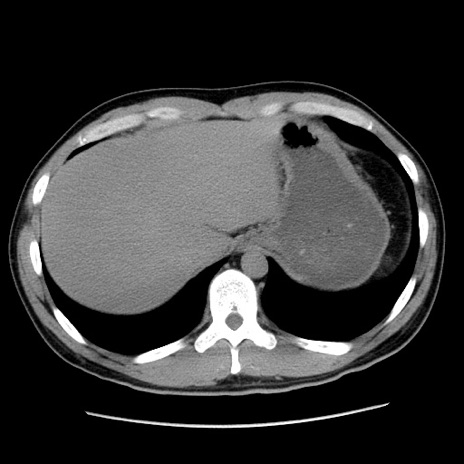

冠状断像

【症例】20歳代 男性

【主訴】心窩部痛

【現病歴】今朝より上腹部痛あり。一旦軽快していたが再度出現したため救急要請。昨日夕に白身の魚を含む刺身を食べた。

【身体所見】BP 136/89mmHg、HR 74/min、BT 37.0℃、腹部:膨満、軟、心窩部に圧痛あり。反跳痛なし、筋性防御なし、腸雑音やや亢進あり。

【データ】WBC 17700、CRP 0.48